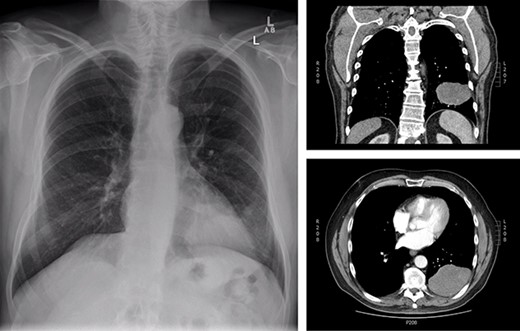

The patient is a 70-year-old man with a 75-pack-year smoking history and occupational asbestos exposure, who presented with back pain and constitutional symptoms in 2019. Physical exam was unremarkable except for hypertrophic pulmonary osteoarthropathy with digital clubbing. Computed tomography chest demonstrated a 18.3 × 17.0 × 13.8 cm left pleural-based tumour, with heterogeneous density and internal calcifications, resulting in compression of the left lower bronchi (Fig. 1). The patient’s medical records revealed that he was originally diagnosed with a left-side pleural SFT in 2013 (Fig. 2); imaging and biopsy at that time revealed a 9.3 cm spindle cell tumour consistent with SFT. The patient was lost to follow-up.

Initial presentation of solitary fibrous tumour in 2013 showing 9.3 × 6.1 cm left-sided pleural-based tumour.